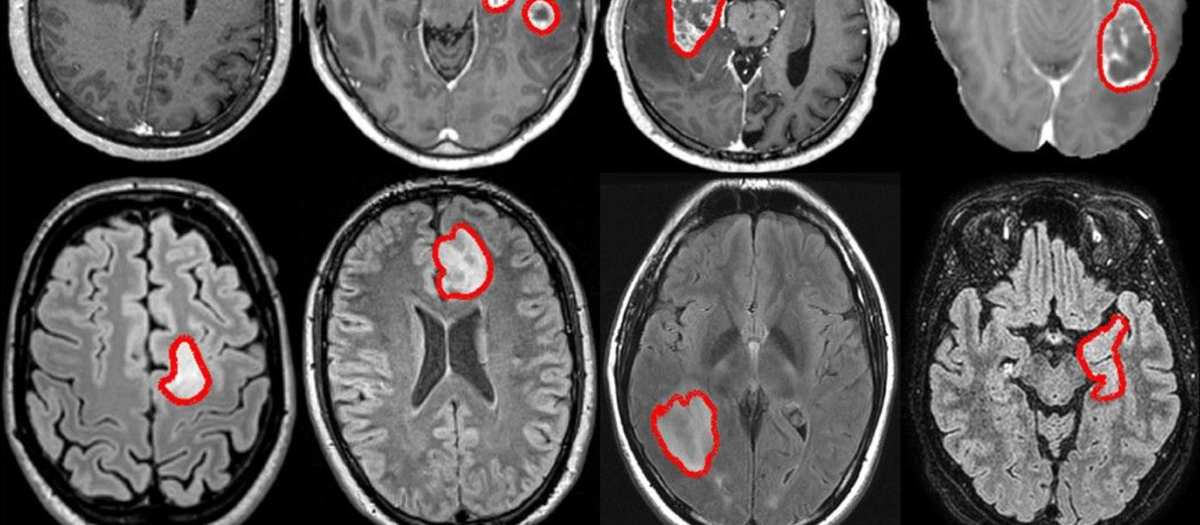

Медицина

- Анализ медицинских снимков (КТ, МРТ, рентген)

- Выявление патологий на ранней стадии